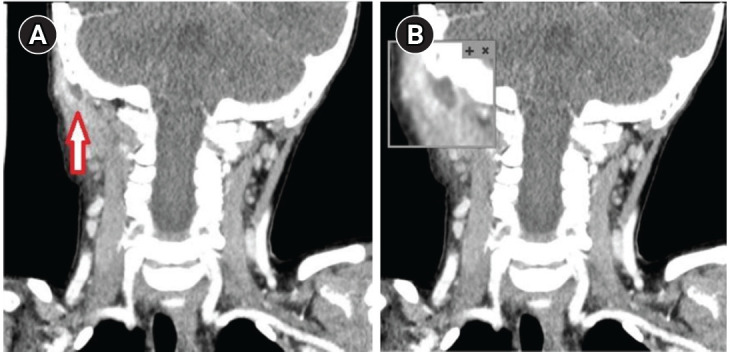

Bezold abscess in a 4-year-old: an exceptionally rare complication of otitis media.

4 岁儿童的贝佐德脓肿:中耳炎的罕见并发症。